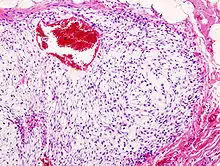

Histopathologic image of chondrosarcoma of the chest wall. Surgical resection of recurrent mass. H & E stain.